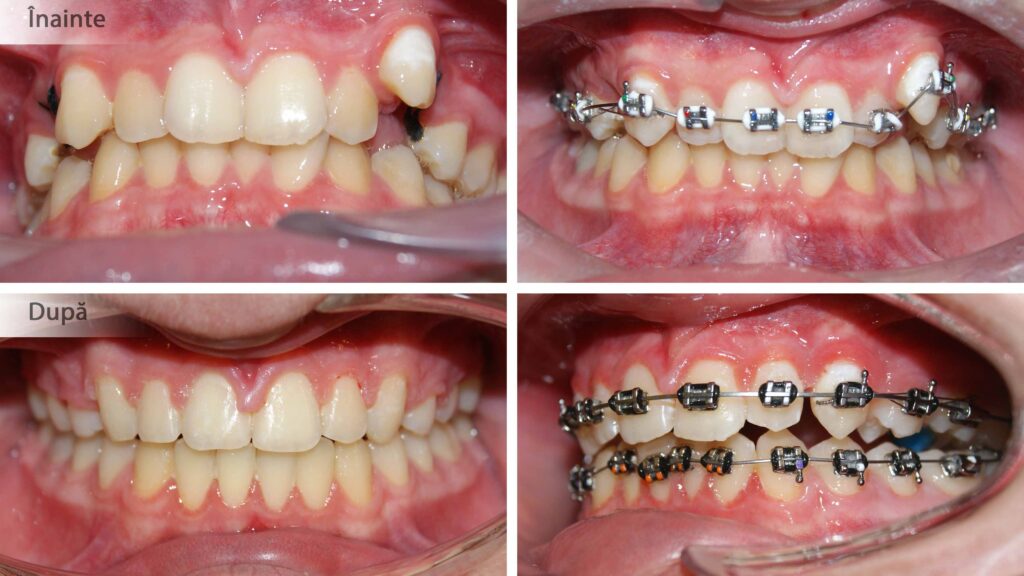

Pozițiile copiilor în somn (cu pumnul sub obraz) timp îndelungat poate determina dezvoltarea asimetrică a oaselor maxilare. Așa cum se vede în poze, cu ajutorul aparatelor ortodontice fixe am îndreptat axele dentare